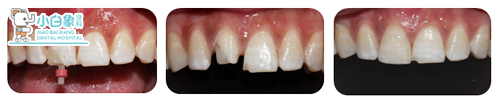

治疗:去暂封,制备桩道,粘结纤维桩,树脂恢复牙体,制备牙体,取像,设计,研磨,试戴,上釉,粘结,戴走。